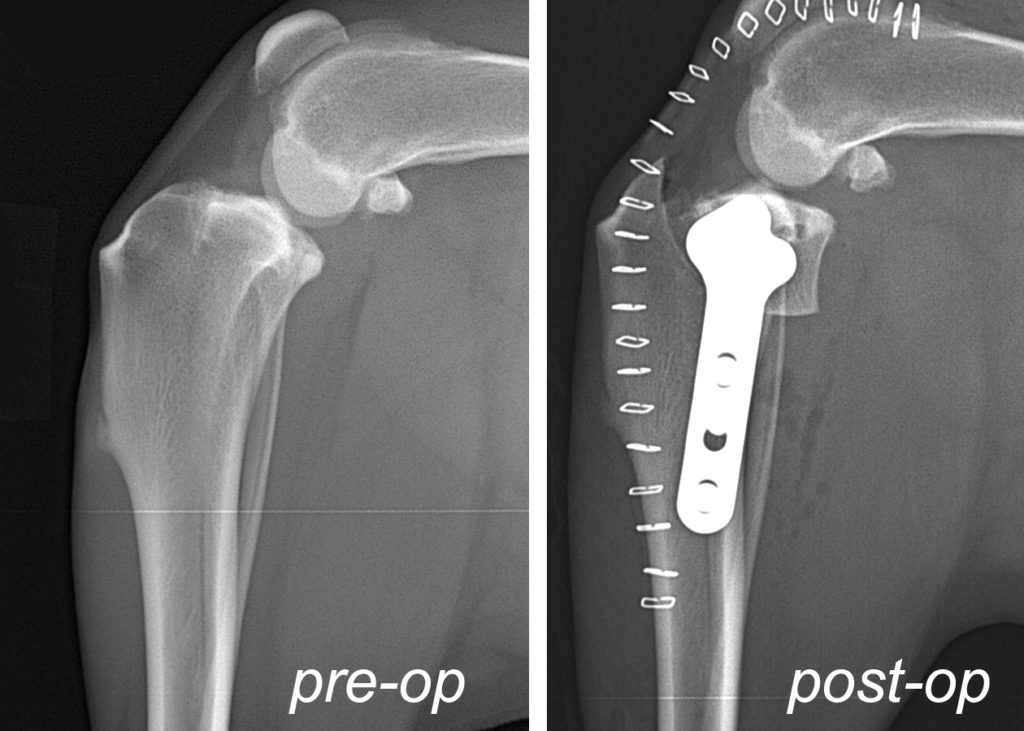

From mooresortho.com

TPLO for Cruciate Ligament Ruptures Moores Orthopaedic Clinic Tplo Surgery Gone Wrong unlike traditional techniques that rely on repairing or replacing the torn ligament, tplo surgery involves restructuring the tibial plateau, the top surface of the shinbone, to modify the angle at which the femur (thigh bone) meets the tibia (shinbone). Learn how to work with your veterinarian to optimize your dog's recovery and explore conservative alternatives. full recovery from. Tplo Surgery Gone Wrong.